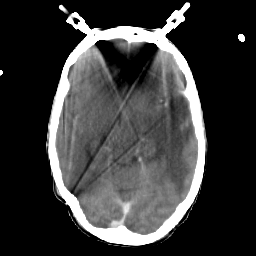

Metastatic bronchogenic carcinoma: Roentgen-ray CT -- Slice #9

[Home][Help][Clinical] Slice 9